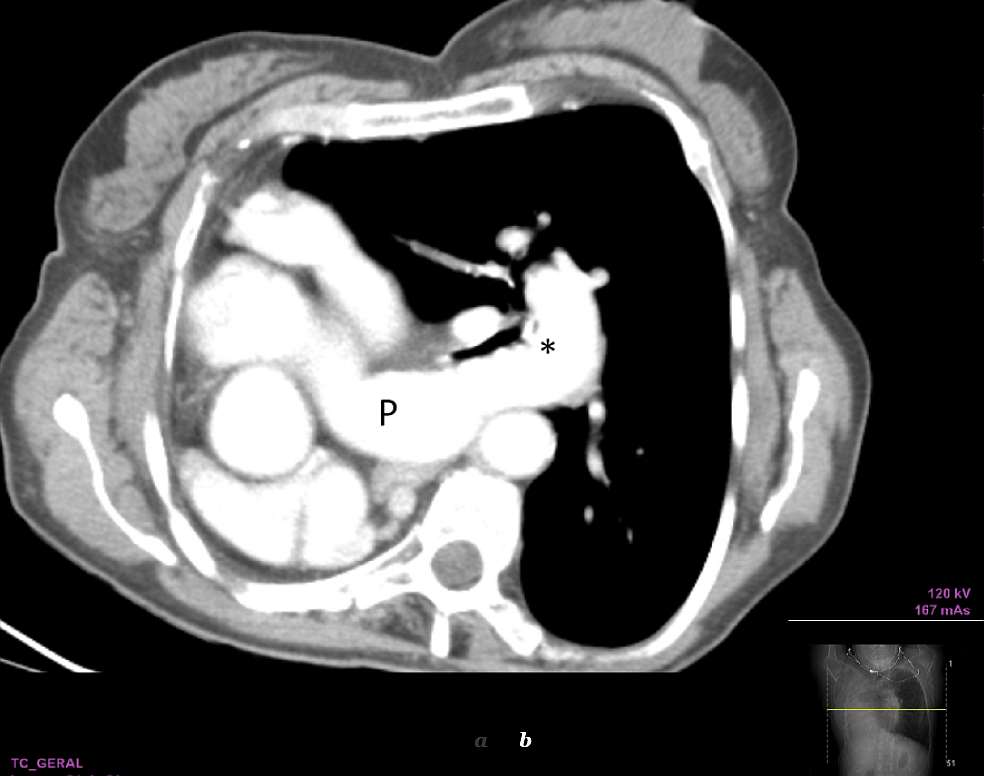

She underwent a CT scan, which showed a complete absence of the right lung, a normal hyperinflated left lung and a clear shift of the mediastinum to the right (dextrocardia). Absence of the right pulmonary artery and of the right main bronchus was also shown.

Imaging studies are essential for the diagnosis of pulmonary agenesis. The diagnosis is usually first suspected on chest radiography, which demonstrates a diffuse opacity of the affected hemithorax and an ipsilateral mediastinal shift [1, 6, 8]. A normal contralateral lung with compensatory hyperinflation and herniation across the midline is a common finding [6]. CT confirms the absence of lung parenchyma, pulmonary artery, and bronchial structures on the affected side [4, 6, 7]. CT angiography and MR angiography are currently the imaging modalities of choice in the diagnosis of this entity [6].